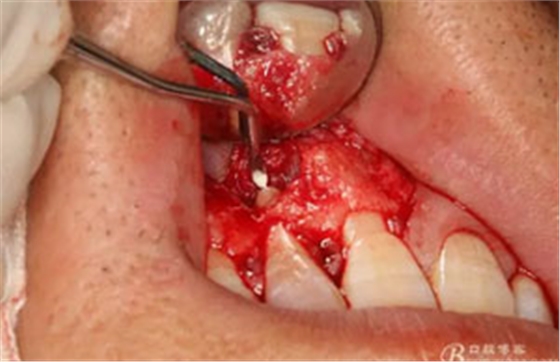

圖15.超聲骨刀修整切除后的根面,使其12根斷面平整光滑。

圖16。專用倒預(yù)備刀頭預(yù)備根尖3mm。